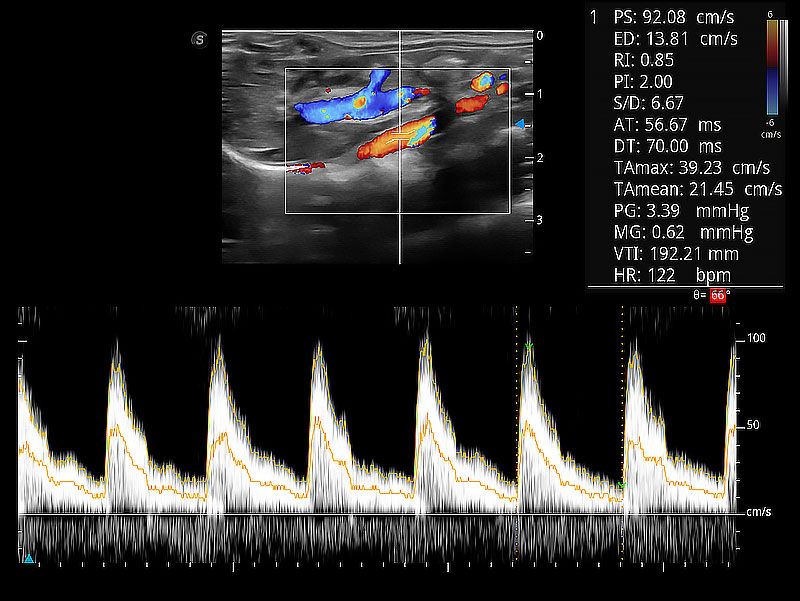

极大提升超低速微细血流的检出能力,同时更精准地滤除软组织和超声信号,为兽用医生提供以往无法通过常规血流获得的疾病诊断信息。

在传统二维血流成像的基础上,呈现血流的立体感,具有动感的生命力之美。即便是微小的血管也能轻松应对,提高了血流的视觉敏感性。

随着取样门位置改变,频谱多普勒包络可进行自动眼踪测量,且可自由配置测量的参数。